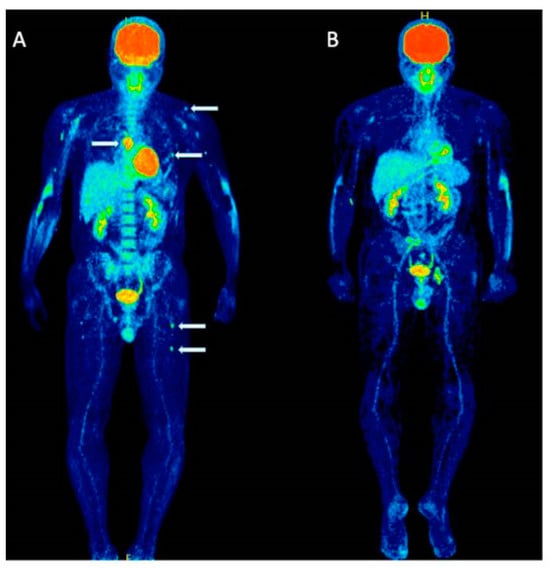

12. Novel PET Radiotracers

The studies are summarized in Table 2. Figure 14 illustrates the use of [68Ga]Pentixafor PET in the evaluation of myeloma.

Figure 14.

This figure illustrates a patient diagnosed with multiple myeloma (MM) of the Ig A λ type, and with increasing free serum light chains. The [68Ga]Pentixafor PET scan displays intense tracer uptake in various locations, including multiple intramedullary lesions (indicated by stars) and extramedullary lesions (indicated by arrows). Copyright © Ivyspring International Publisher. Reproduction is permitted for personal, non-commercial use, provided that the article is in whole, unmodified, and properly cited. PMCID: PMC5196897, PMID: 28042328 [64].